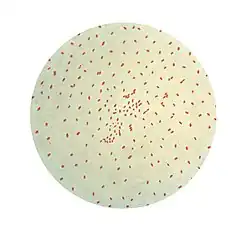

Methods used in laboratory diagnosis include culturing of nasopharyngeal swabs on a nutrient medium (Bordet–Gengou medium), polymerase chain reaction (PCR), direct fluorescent antibody (DFA), and serological methods (e.g. complement fixation test).[34] The bacteria can be recovered from the person only during the first three weeks of illness, rendering culturing and DFA useless after this period. However, PCR may have some limited usefulness for an additional three weeks.